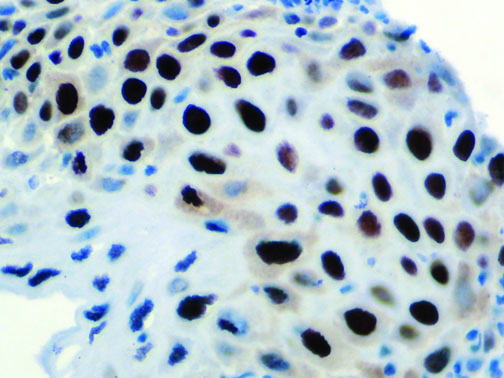

It is the ICU physician who is most likely to witness one of the deadliest manifestations of the abnormal immunological response, the cytokine storm syndrome (CSS). This response is also referred to by some as the cytokine release syndrome (CRS). CSS is characterized by continuous activation and expansion of macrophage and lymphocyte populations, which secrete large amounts of cytokines, causing the cytokine storm. This massive cytokine release is akin to hemophagocytic lymphohistiocytosis (HLH) disease, a syndrome characterized by initial unchecked and persistent activation of cytotoxic T lymphocytes and NK cells.

Clinical and laboratory manifestations of HLH include fever, enlarged liver and/or spleen, neurologic dysfunction, coagulopathy, liver dysfunction, cytopenias (i.e., low levels of erythrocytes, leukocytes, and/or platelets), hypertriglyceridemia, hyperferritinemia, hemophagocytosis, and eventually diminished NK cell activity as the immune system becomes progressively paralyzed. HLH can be familial (primary HLH) or secondary to another disease process (sHLH), such as rheumatic disease, in which it is referred to as macrophage activation syndrome (MAS, characterized by elevated ferritin).